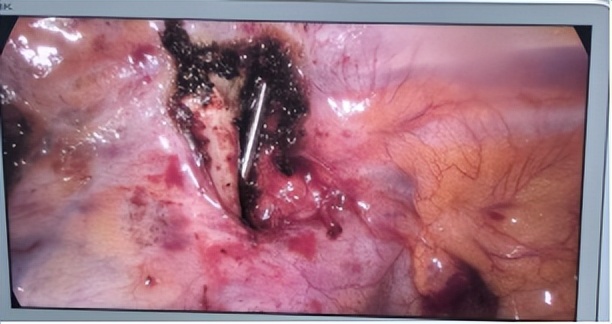

在手术麻醉部和手术室的通力配合下,胸部外科副主任王律团队为张先生实施了手术。术中,仅通过一个2cm的小切口,在胸腔镜下进行了仔细搜寻。由于钢针部分扦插入锥体,位置深,手术难度高。王律副主任凭借经验,通过腔镜器械逐步松动移位钢针后,取出了全部断裂移位的钢针,成功化解了钢针可能引发的内出血、感染等风险。

胸腔镜下移位断裂的钢针

取出的断裂的钢针